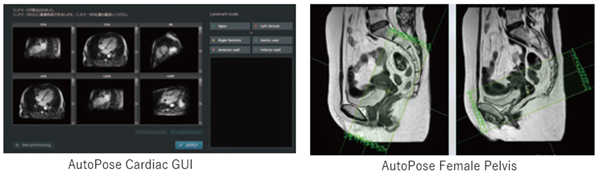

スライスライン設定サポート機能AutoPose※6

AutoPoseは全身幅広く進化した対象部位

VINCENT※7 で蓄積した豊富なCTのデータをAI技術でMRI画像に変換する技術を確立しました。この技術と臓器セグメンテーション開発で構築したCNNライブラリをMRI位置決め開発に活用し,多くの部位で精度の高い位置決め機能※8 を製品化しました。

※6 開発にDeep Learningを活用しています。導入後に自動的に装置の性能・精度が変化することはありません。

※7 3D画像解析システムSYNAPSE VINCENT